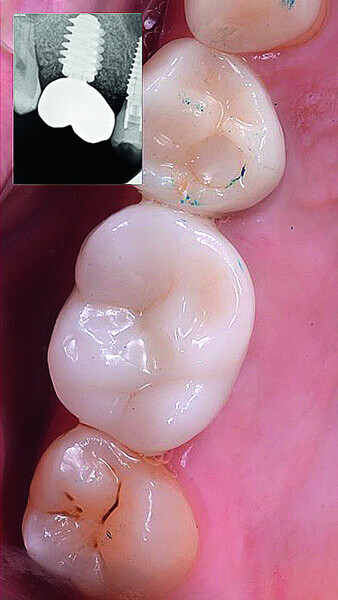

Digital workflow and application of PRF and ozone therapy in oral rehabilitation